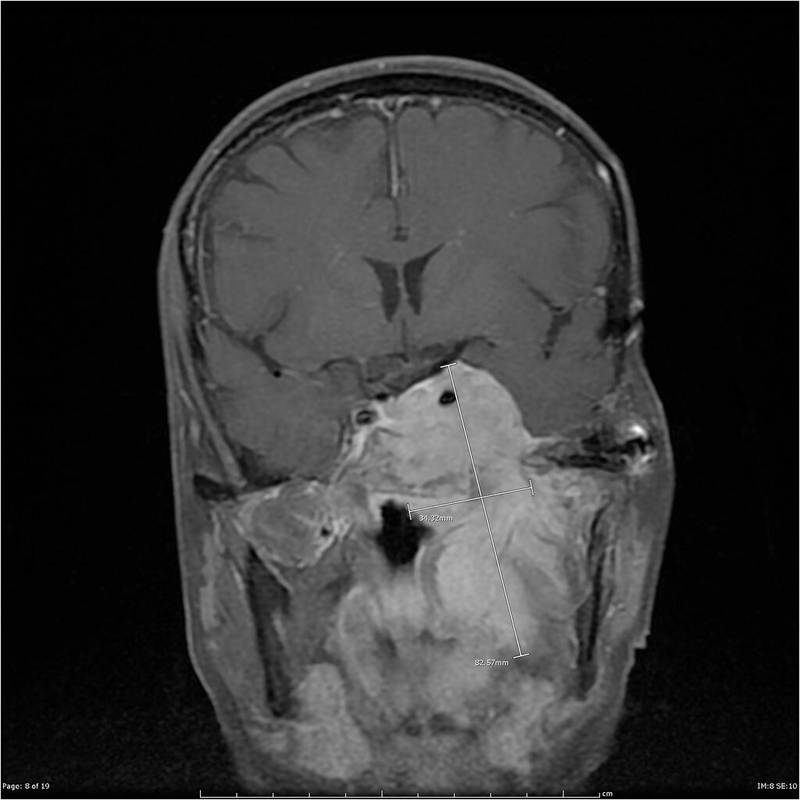

Cách chẩn đoán u màng não nền sọ sẽ dựa trên một số phương pháp kiểm tra và thực hiện một số xét nghiệm. Đầu tiên, bác sĩ sẽ khám lâm sàng, hỏi về các triệu chứng. Sau đó, bác sĩ chuẩn đoán bệnh thông qua hình ảnh của một số kỹ thuật như:

Trong quá trình điều trị cần phải theo dõi, kiểm tra khối u thường xuyên. Theo nghiên cứu, các khối u màng não nền sọ có kích thước nhỏ dưới 2 cm được xác định thông qua chụp cộng hưởng từ (MRI), không có triệu chứng lâm sàng, thì sẽ được chỉ định theo dõi. Để theo dõi sự phát triển của khối u, bác sĩ sẽ chỉ định người bệnh đến tái khám định kỳ 3 - 6 tháng qua chụp cộng hưởng từ. Trên thực tế, đối với các u màng não lành tính thì chỉ phát triển thêm về kích thước từ 0,2 - 0,5 mm/năm.